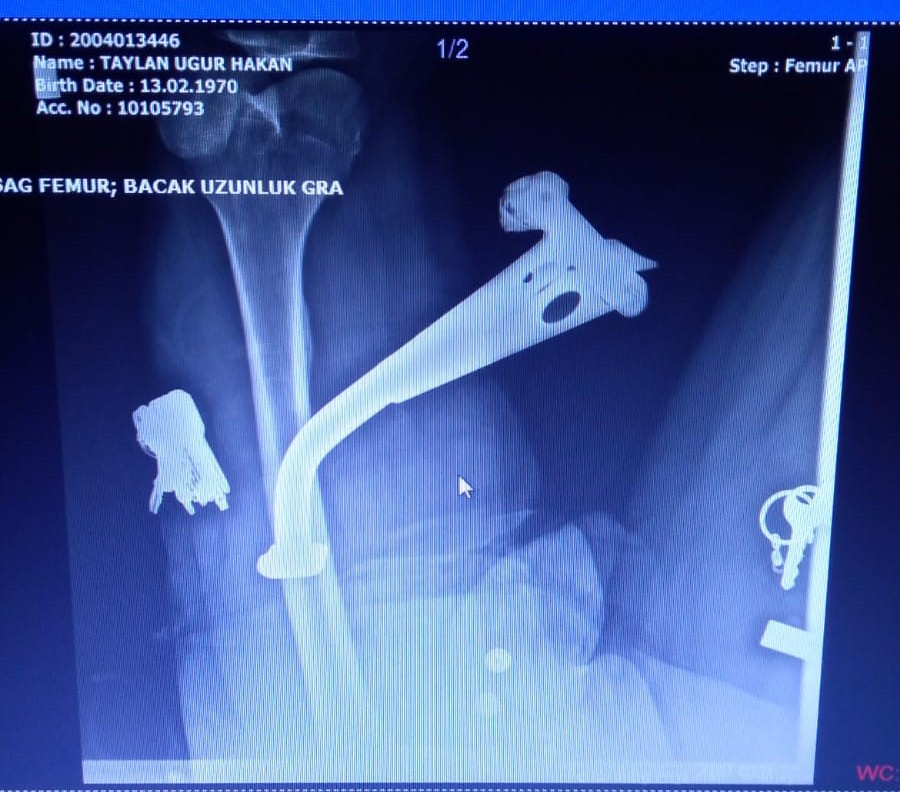

İzmir'in Çeşme ilçesindeki motosiklet kazasında, bacağına motosikletin ayaklığı saplanan Uğur Hakan Taylan, Çeşme Alper Çizgenakat Devlet Hastanesi'nde geçirdiği operasyonla ayaklıktan kurtarıldı.

Ambulansla Çeşme Alper Çizgenakat Devlet Hastanesi'ne kaldırılan Uğur Hakan Taylan'a hastanede ilk müdahale yapılırken, Ortopedi ve travmatoloji uzmanı Op. Dr. Osman Refik Çetin de hastaneye gelerek, Taylan'ı ameliyata aldı. Bu duruma sağlık çalışanları da şaşırdı. Taylan'a lokal anestezi yapılarak, baldırına saplanan motosiklet ayaklığı çıkarıldı. Op. Dr. Çetin, Uğur Hakan Taylan'ın baldırındaki sinirlerin ve damarların zarar görmediğini belirterek, hastanın iyi durumda olduğunu ve birkaç gün sonra da dikişlerinin alınacağını söyledi.